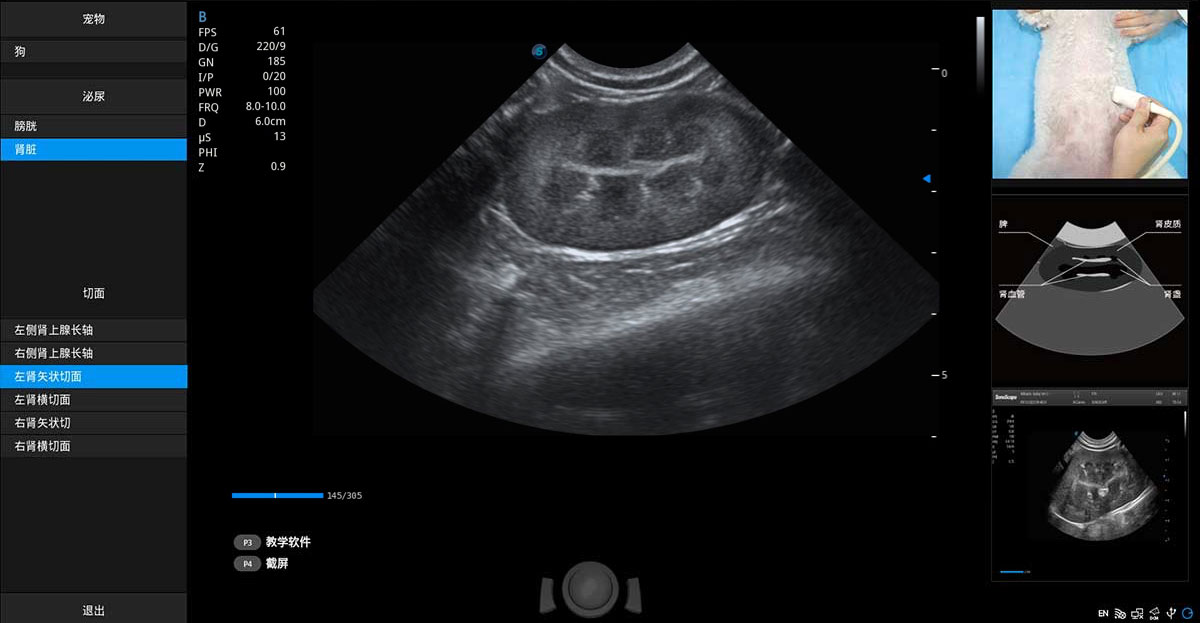

ProPet 80 專為動(dòng)物醫(yī)生設(shè)計(jì),對(duì)不同的動(dòng)物體型和生理結(jié)構(gòu)作出了針對(duì)性的優(yōu)化。通過動(dòng)物影像專用軟件,可滿足個(gè)性化的應(yīng)用需求,幫助動(dòng)物醫(yī)生獲得更精確的診斷數(shù)據(jù)。

為精細(xì)結(jié)構(gòu)及組織邊緣提供高清晰度的圖像和更大的成像視野。幫助減輕醫(yī)生的用眼疲勞,快速精準(zhǔn)獲得測(cè)量的數(shù)據(jù)。

提供解剖示意圖、標(biāo)準(zhǔn)超聲圖像、掃查手法涂和操作者實(shí)時(shí)檢查圖像,指導(dǎo)操作者進(jìn)行標(biāo)準(zhǔn)切面的正確掃查。